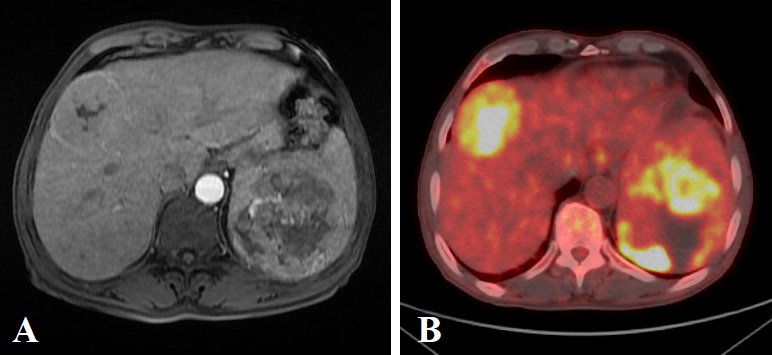

In the HPB council, the case was evaluated as an undifferentiated (embryonal) sarcoma originating from the liver and metastasizing to the spleen, and chemotherapy was decided. According to our literature review, it is the first case in which UESL was detected in the form of a synchronous lesion in the liver and spleen in an elderly patient. The patient’s postoperative period was uneventful, but he refused adjuvant chemotherapy.Follow up controls of the patient were performed with USG and abdominal CT at 3-6 month intervals. Malignant cells were observed in the bone marrow examination performed to investigate the etiology of anemia 17 months later. Abdominal CT performed in the same period revealed recurrent lesions in the liver, abdomen, and lung (Figure 4). The patient accepted chemotherapy and was discharged with a chemotherapy protocol including six cycles of gemcitabine plus docetaxel combination. Despite the partial regression of his lesions, he died at the postoperative 30th month with intra-abdominal recurrences and lung metastases.

Figure 4

Figure 4. Abdominal CT at the postoperative 18th month shows local recurrence and new lesions located in the liver and left upper quadrant (arrows).